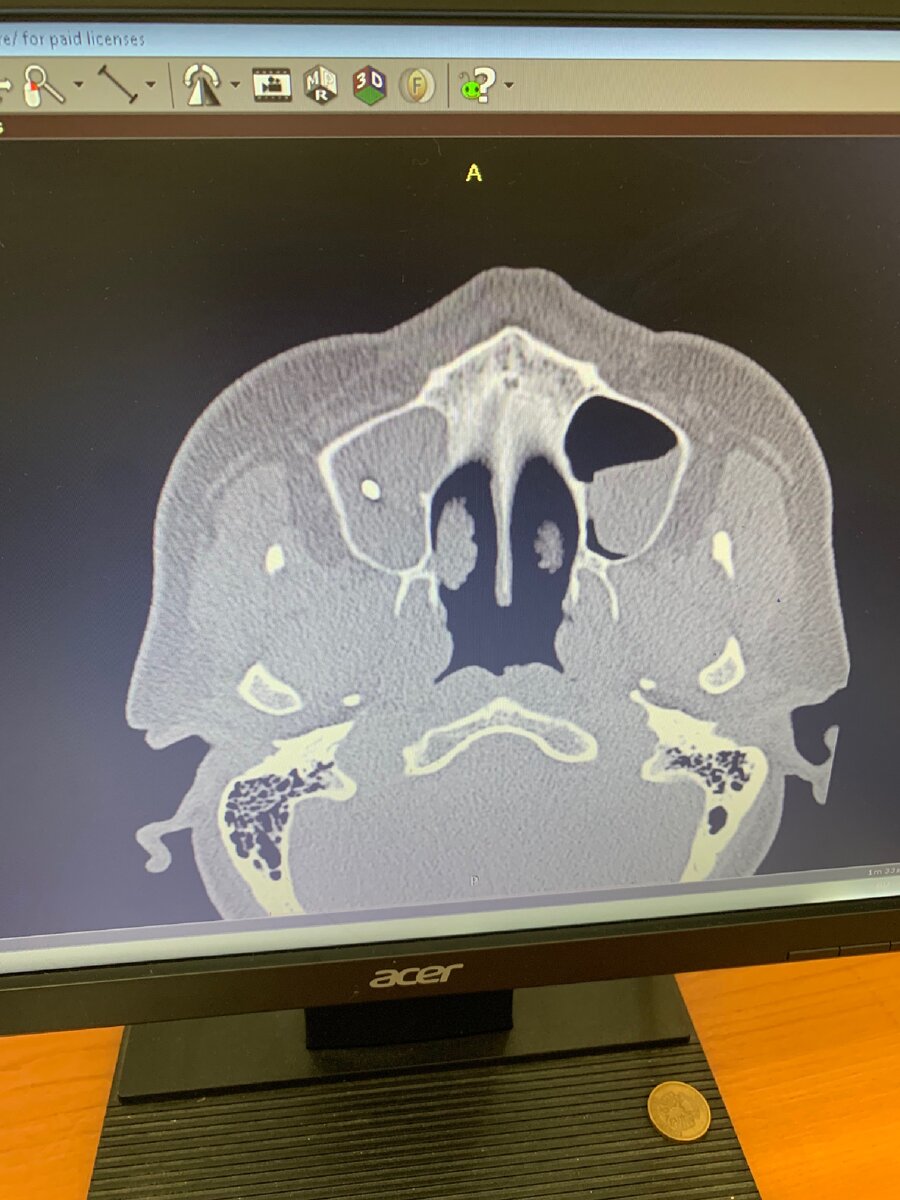

Если есть возможность и необходимость, рекомендовано проведение компьютерной томографии этой зоны, что будет более информативным. Это исследование покажет :

1. утолщение слизистой оболочки носа и синусов

2. искривление носовой перегородки

3.воспаление внутри пазух

4.полипы, гранулемы и кисты слизистой оболочки

5.опухоли в околоносовых пазухах

6.скопление гноя, эксудата в синусах

7.инородные тела